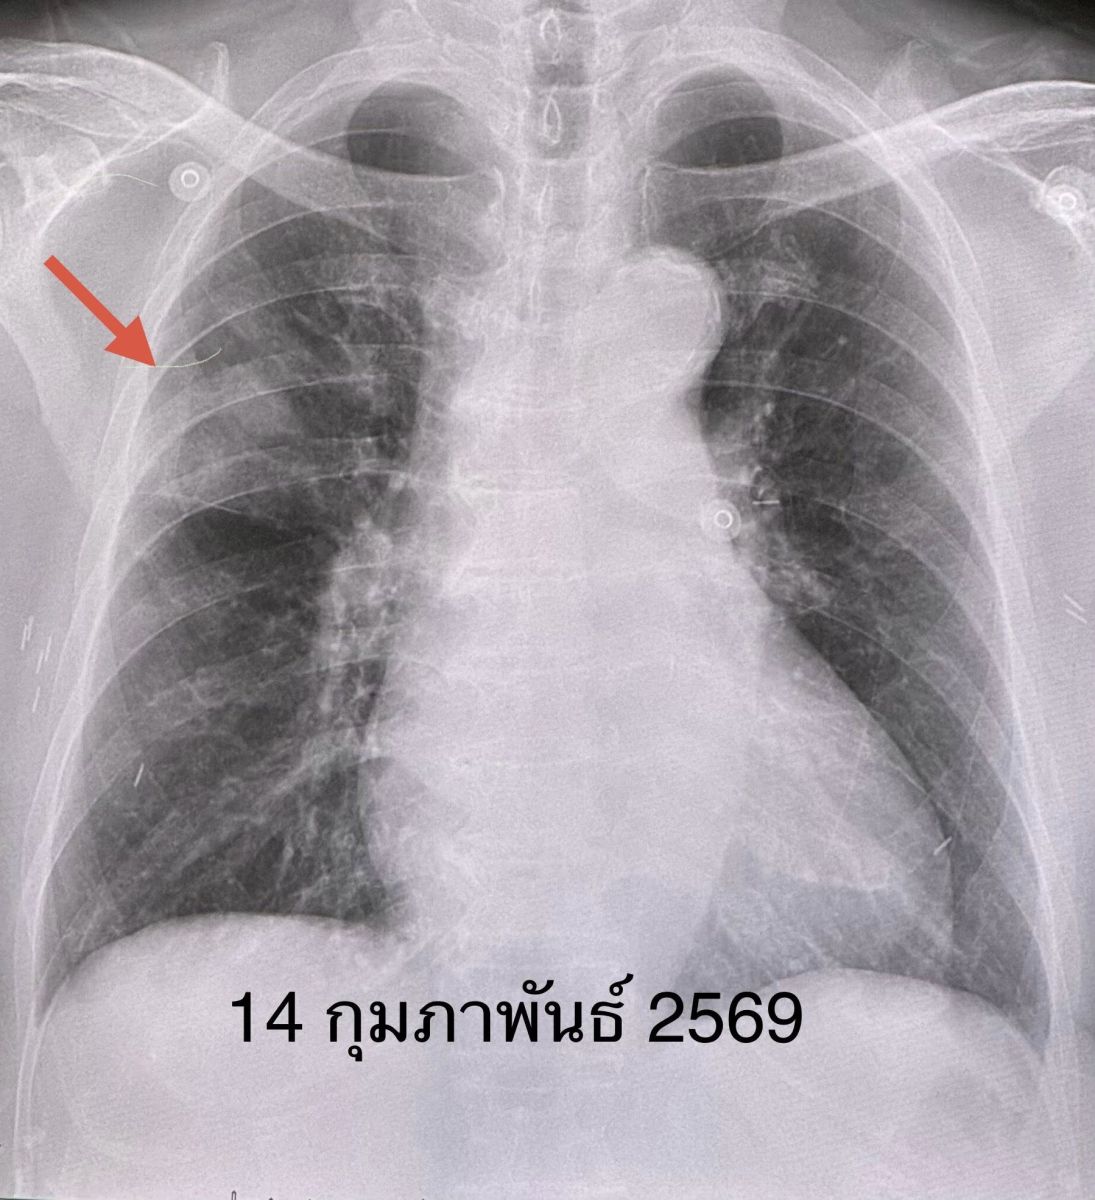

ผลตรวจร่างกาย ไม่มีไข้ ระดับออกซิเจนที่ปลายนิ้ว 96% หัวใจเต้นเร็ว 130 ครั้ง/นาที หัวใจเต้นผิดจังหวะ ฟังปอดปกติ ทำคลื่นไฟฟ้าหัวใจ พบหัวใจห้องบนเต้นระรัว (Atrial fibrillation) ตรวจหัวใจดัวยคลื่นเสียงความถี่สูง (Echocardiogram) ไม่พบความผิดปกติ เจาะเลือด เม็ดเลือดขาวในเลือดปกติ ส่งเลือดเพาะเชื้อ ไม่ขึ้นเชื้อแบคทีเรีย เอกซเรย์ปอด มีฝ้าขาวลักษณะคล้ายก้อนที่ปอดข้างขวากลีบบน แยงจมูกส่งตรวจสารพันธุกรรม RT-PCR พบเชื้อโบคาไวรัส (Bocavirus)

เคสนี้แพทย์วินิจฉัย ว่า โบคาไวรัส (Bocavirus) ทำให้เกิดปอดอักเสบ และภาวะหัวใจห้องบนเต้นระรัว (Arial fibrillation) ในผู้สูงอายุรายนี้ ซึ่งมีโรคประจำตัวเบาหวาน และไขมันสูง หลังให้ยา cordarone หัวใจกลับมาเต้นเป็นปกติ ให้การรักษาตามอาการ ไอลดลง ไม่มีเสมหะ ไม่มีไข้ ติดตามเอกซเรย์ปอดกลับมาปกติในเวลา 6 วัน